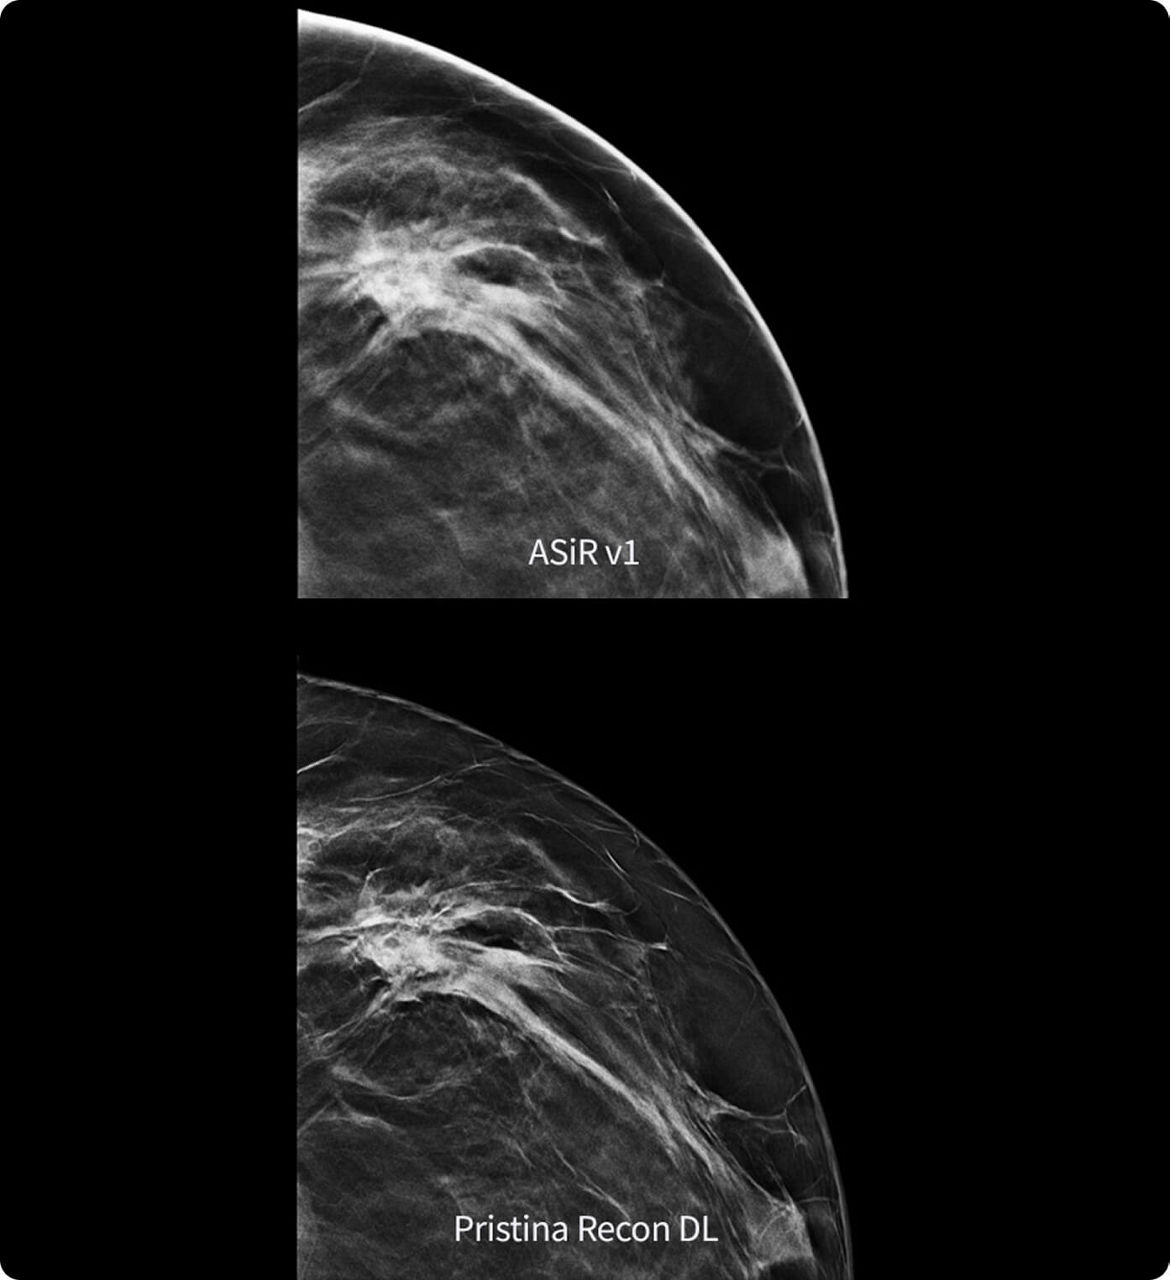

Sharp, clear, precise

Pristina Recon DL reconstructs with scientific precision, transforming breast images into pristine, clear volumes. It uses two deep learning models to improve image quality without changing the acquisition.

The improvement is easy to see, with radiologists surveyed consistently preferring its sharpness1,2 and lesion conspicuity1,2.

1. Preference study performed on 140 study cases with 8 MQSA-approved radiologists, trained on clinical image quality by ACR, comparing Pristina Recon DL to ASiR v1.

2. Reader performance evaluation on 19 680 reads with 8 readers using modeled clinical data comparing Pristina Recon DL and ASiR v1.